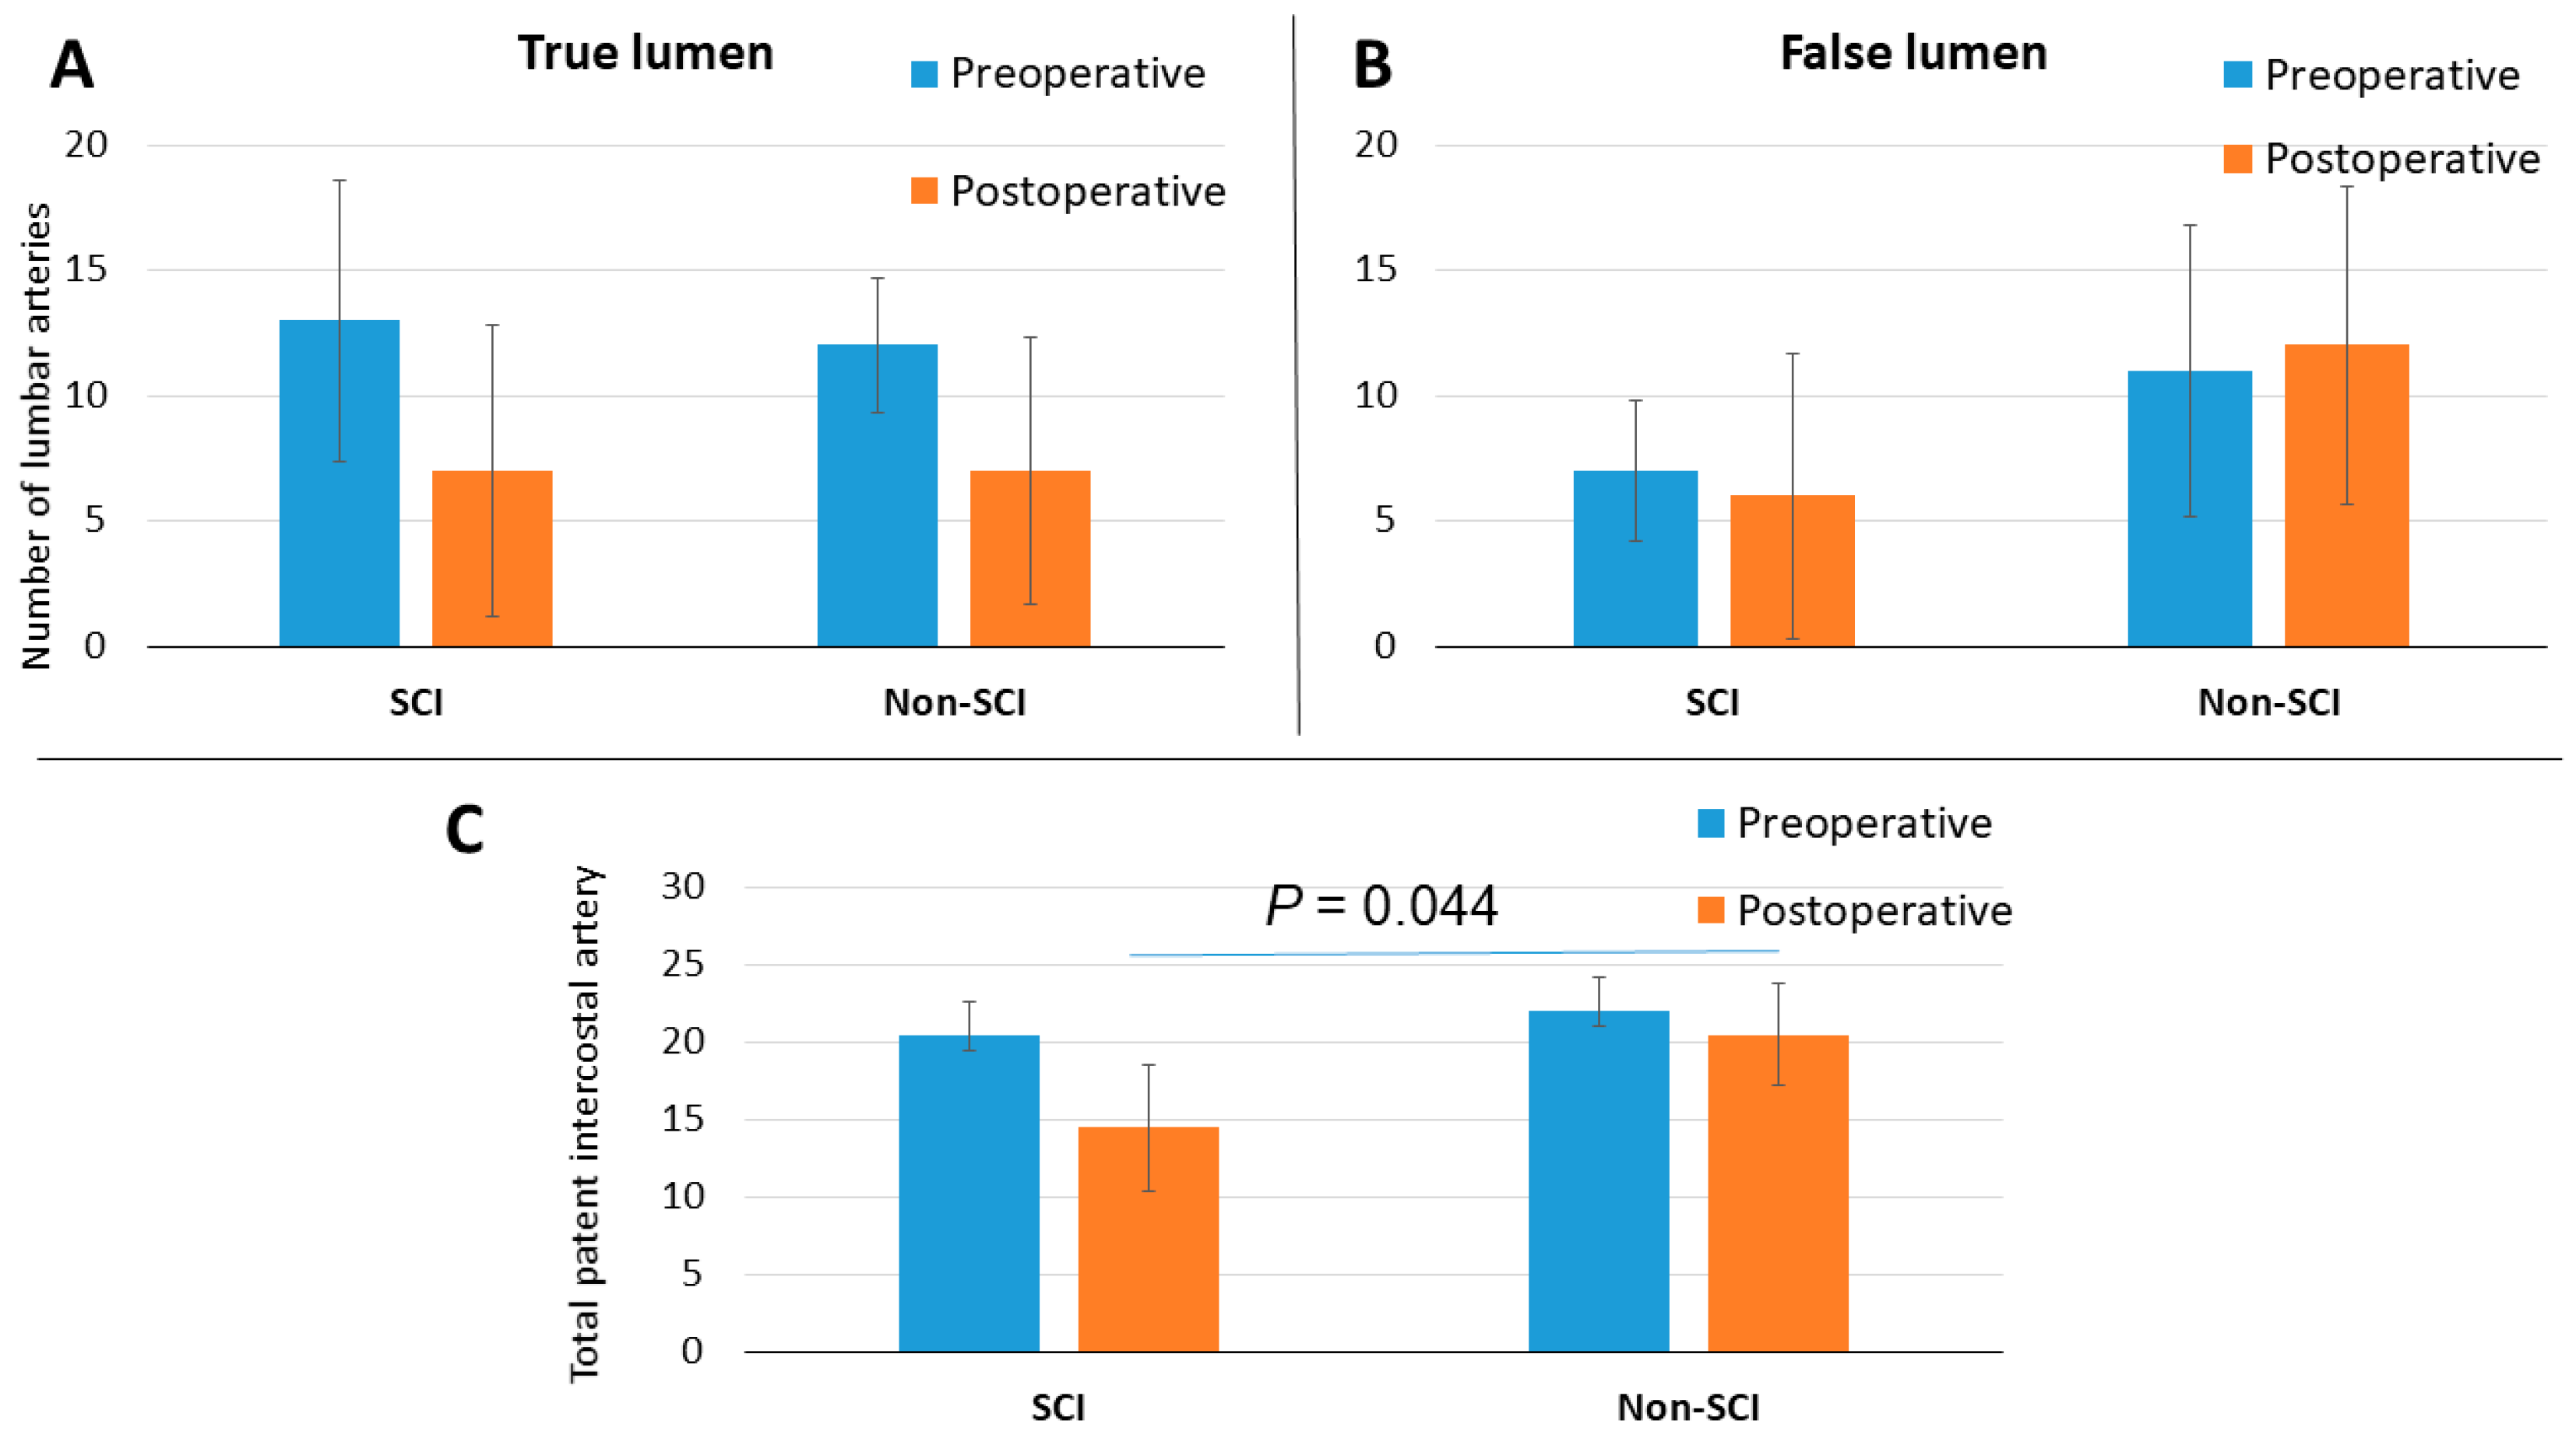

3. Results